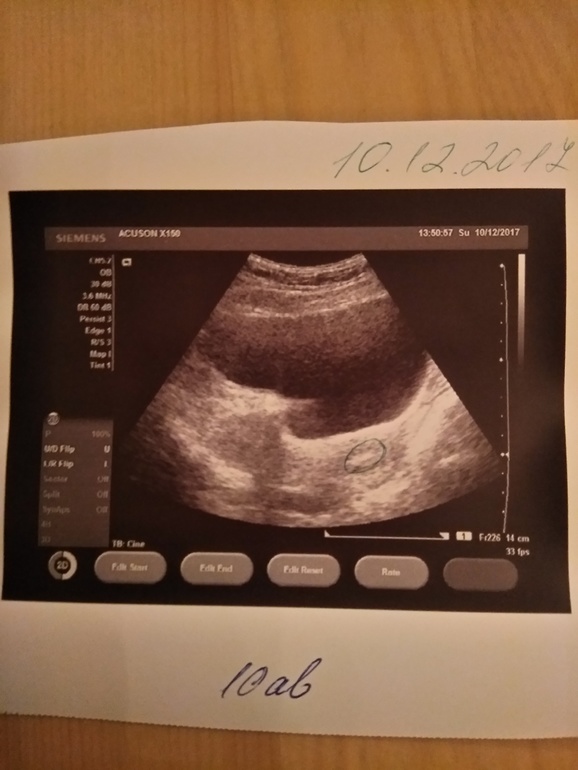

10.12.17 - Перенос!

26.12.17 - сделала УЗИ. ПЯ в матке, диаметр 4мм))) 10 января ещё раз УЗИ уже с сердечком, ну и ХГЧ повторю.